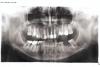

Мирель Опубликовано 8 апреля, 2013 Поделиться Опубликовано 8 апреля, 2013 Здравствуйте. У меня глубокий прикус.(первое фото) Мне ставят коронки на все зубы и при помощи этого немного приподнимают прикус. На переднии верхнии 8 зубов я буду ствить цирконий, на все остальные металлокерамику. 1. Под цирконий решили нервы не удалять, на те которые со штифтами ставить мостом, а на остальные по самостоятельной коронке ( Можно ли так? или следует удалить нервы ...?) 2. металлокерамику ставят в три секции (на нижних зубах, на верхних то что останется тоже под секции)3. сверху с внешней стороны подрезали десну и десневой "сосочек" или "язычек" (незнаю как правильнее). Через день десневой "язычок" с внутренней стороны опух и болит. Врач сказал что он воспален т.к. его травмировали и дня через 3 пройдет. Прошла неделя, опухоль и боль не прошла, гноя нет. Что с ним делать? Почему он опух? (на втором фото стрелочка)4. Нужно ли перелечивать и переделывать все старые пломбы? Ссылка на комментарий